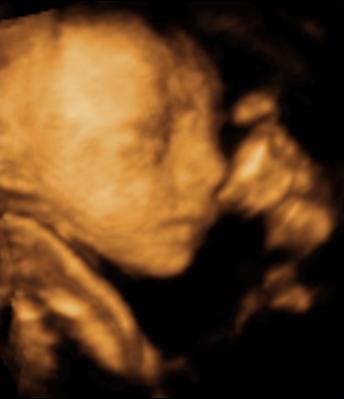

A második képen nyitva van a szeme is